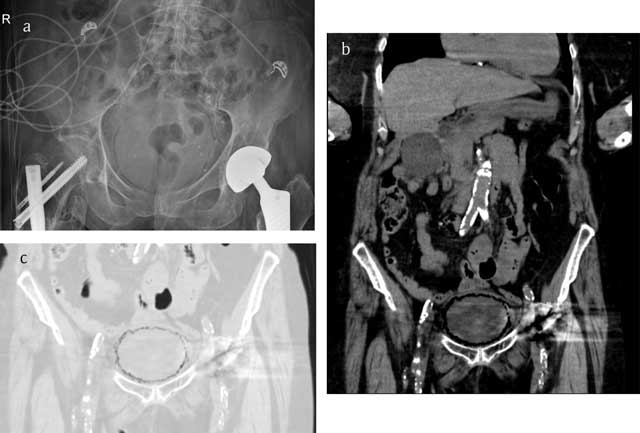

Figure 1

Conventional radiograph (a) in a case of emphysematous cystitis shows sharply demarcated, curvilinear areas of increased lucency in the pelvis. Computed tomography (b, c) images more clearly reflect the cobblestone aspect of intramural gas delineating the bladder wall, often likened to a “beaded necklace” appearance.

A 71-year-old woman was brought to the emergency room because of confusion and coffee ground vomitus. Physical examination was unremarkable. The abdomen was soft and non-tender. Laboratory tests showed normochromic normocytic anemia, elevated inflammatory parameters and elevated kidney function tests. Urine analysis showed numerous red blood cells, white blood cells and bacteriae. Abdominal X-ray showed a curvilinear area of radiolucency delineating the bladder wall (Figure 1a). Non-contrast enhanced computed tomography (CT) of the abdomen revealed multiple gas pockets within the bladder wall (Figure 1b and 1c). A diagnosis of emphysematous cystitis was made and the patient was started empirically on intravenous piperacillin/tazobactom. Urine culture grew E. Coli and treatment was switched to intravenous levofloxacin. There was gradual clinical improvement of the patient. Control ultrasonography performed the week after admission showed a normal bladder wall.

Because of the nonspecific presentation, imaging plays an important role in the diagnosis. Plain abdominal X-rays can show a rim of gas lucency outlining the bladder wall and/or air fluid levels within the bladder. Computed tomography (CT) can more accurately define the extent and severity of the disease, can detect cases that are not apparent on plain radiography and can help in differentiating emphysematous cystitis from colovesical fistula, intra-abdominal abcesses, neoplastic disease or emphysematous pyelonephritis.